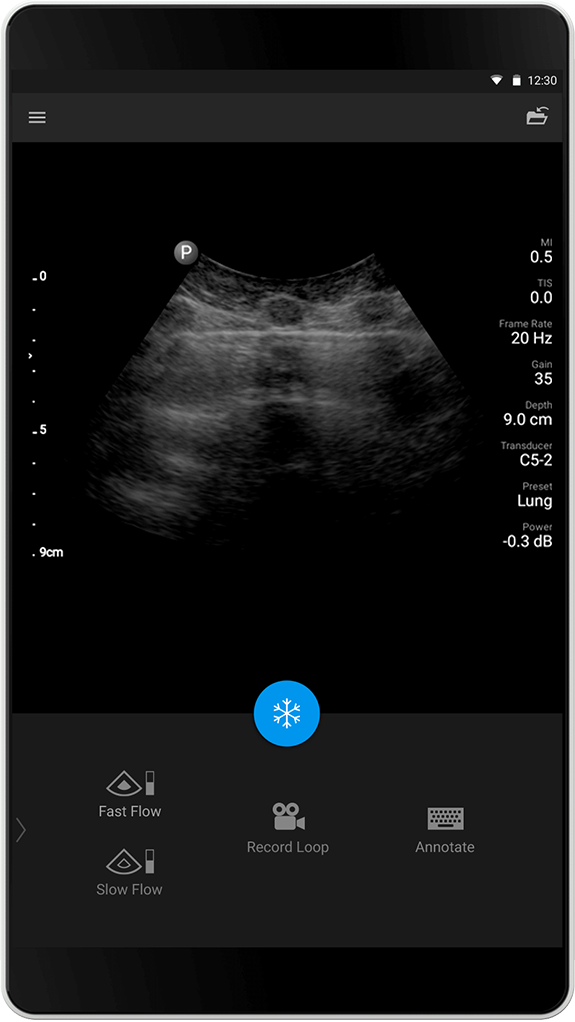

Forhåndsinnstillingen Lung (Lunge) er optimalisert for å fremheve artefaktene som er forbundet med lungeavbildning, og muliggjør enkel visualisering av lungeglidning ved det pleurale grensesnittet. Det vises avanserte avbildingsteknikker (SonoCT, Harmonics og Xres) er ikke aktive/utkoblet i dette presettet/forhåndsinstillingen for bedre fremstilling av tegn som «A-linjer» og «B-linjer».